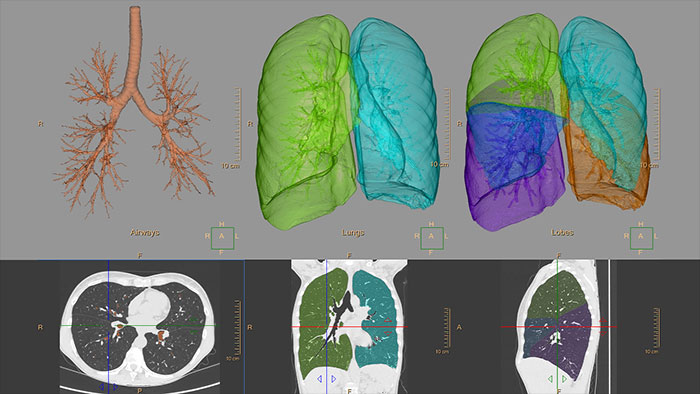

Aplikacja kliniczna umożliwia wizualizację i analizę ilościową destruktywnego procesu choroby śródmiąższowej płuc (np. rozedmy płuc). Wspomaga ona pracę użytkownika, przeprowadzając go przez procesy analizy dróg oddechowych, przeglądu i pomiaru wielkości światła dróg oddechowych oraz oceny zaklinowanego powietrza.

Aplikacja CT COPD służy do ilościowej obserwacji destruktywnego procesu choroby śródmiąższowej płuc (rozedmy płuc) oraz lokalizacji obszarów płuca objętych chorobą.